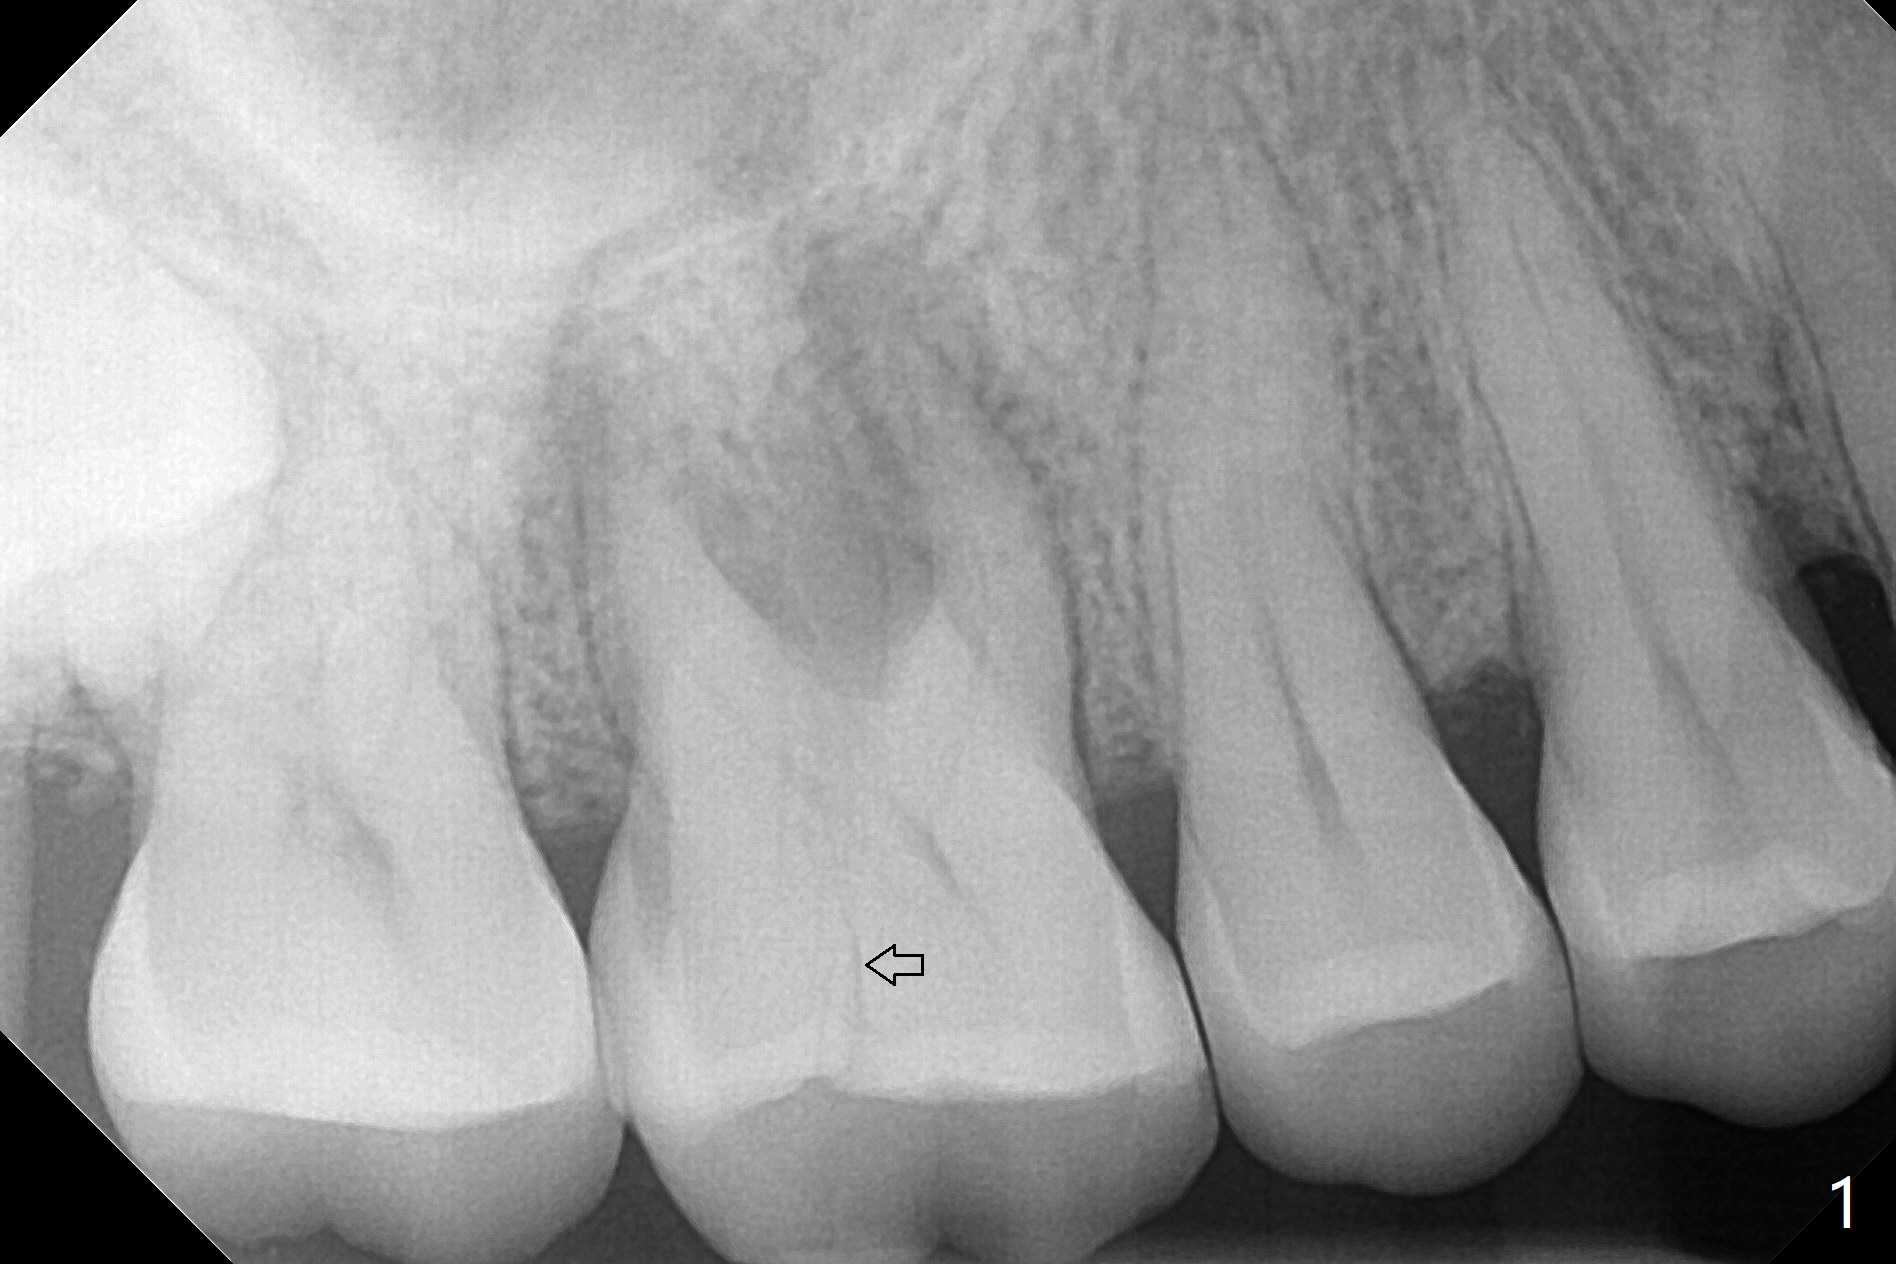

A 53-year-old woman has crack tooth symptom at #3 with apparently a vertical crack line on PA (Fig.1 arrow), suggesting bruxism. The latter may be easily associated with abutment screw loosening. To avoid this complication, a tissue-level implant will be placed (Fig.3). After extraction, the initial depth of osteotomy in the septum will be 7 mm (Fig.2). Find a pointed drill. Take preop photos to show the possible buccal crack line.